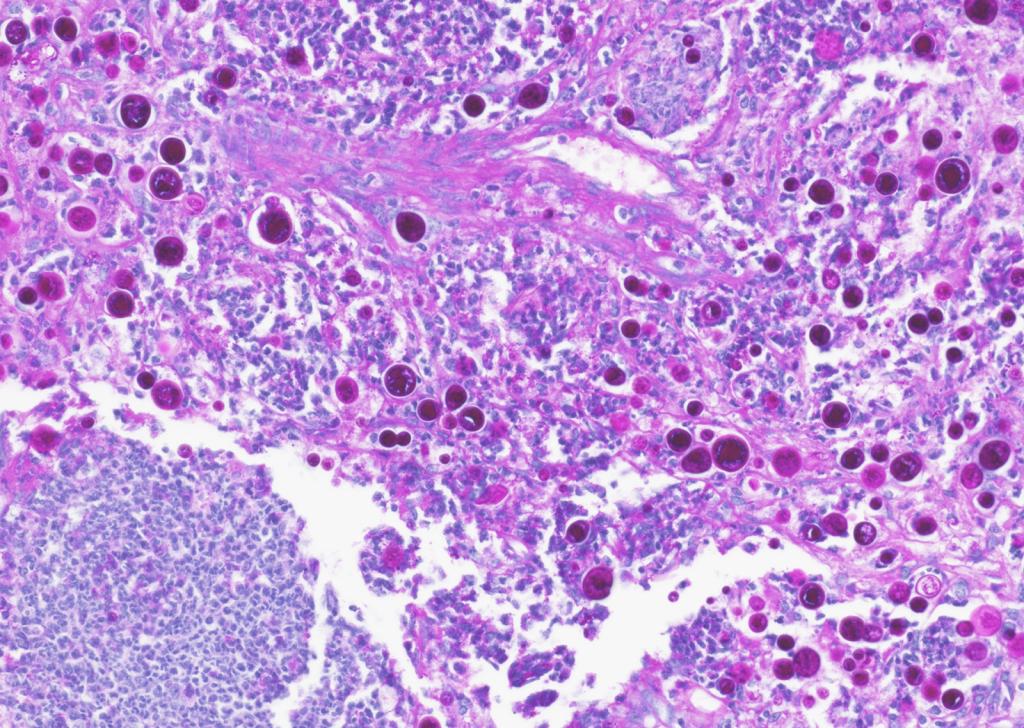

Most people who breathe in cocci spores — about six in 10 — won’t develop symptoms. But the 40% of exposed people whose immune systems can’t or won’t fight off the fungus develop symptoms such as fatigue, muscle aches, coughing, and rash that can last weeks or months. In the 5 -10% of symptomatic cases where the fungus invades the vital organs, the death rate is as high as 25%. The pathogen is so powerful that the U.S. army weighed whether to develop it into a bioterrorism weapon in the 1960s. (A histological slide of valley fever spores in the lung tissue of a dog is shown below.)

Image

A histological slide of valley fever spores in the lung tissue of a dog.

Lisa Shubitz // Valley Fever Center for Excellence